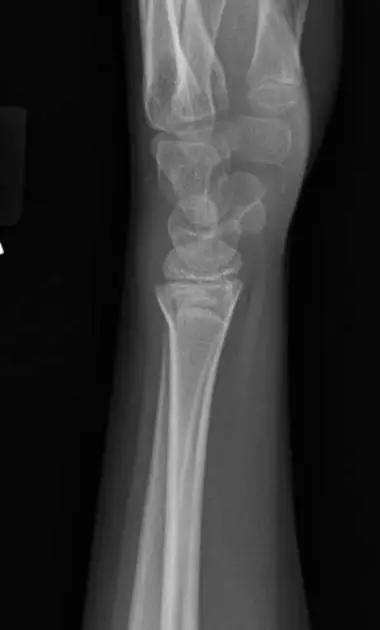

4. Die-punch 骨折

远端桡骨的关节内骨折,伴有月骨陷窝背侧表面的压迫。也称月骨负荷骨折或模具冲压骨折,指挠骨的月骨对应面发生的向近侧的压缩骨折,有不与周围关节囊相连的游离关节面骨折块。

Die-punch 骨折(来源:radiology assistant)